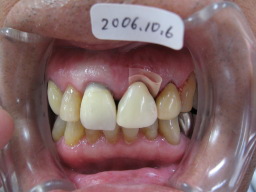

| 左上顎前歯(21)の歯の根が割れて歯ぐきが 腫れ痛みが生じています。 |

| かぶせ物(補綴物)をはずすと根が割れているの がわかります。 |